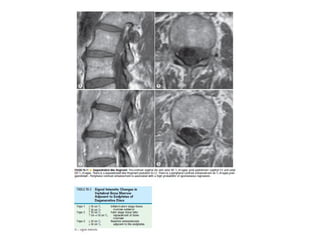

The spine is made up of vertebrae separated by intervertebral discs that allow movement and provide shock absorption. Diagnostic imaging plays an important role in evaluating the spine for conditions like fractures, disc herniations, spinal stenosis, and tumors. Imaging modalities like X-rays, CT scans, MRI, and bone scans can detect abnormalities and aid physicians in diagnosing and treating various spinal disorders.